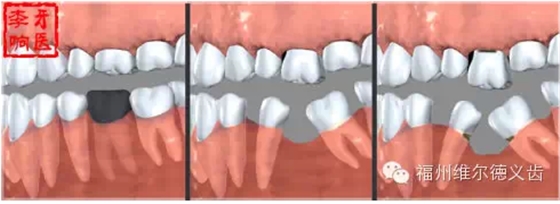

你說種牙太貴我不鑲了,我挺著,時間久了,兩邊的牙向缺牙的地方倒了,對應(yīng)的咬合面上的牙齒伸長了,這時候會發(fā)現(xiàn)缺牙附近前后左右的牙吃東西都塞牙,長期的塞牙造成其他牙齒的齲壞,開始了上述的循環(huán),這時候的治療費用不是一顆牙的問題,要乘上壞牙的數(shù)量,更貴了。什么?你深感缺牙不便,又想鑲了?有些可以先正畸恢復(fù)到剛?cè)毖罆r候的狀態(tài),再鑲,當(dāng)然,正畸又有一筆費用。有些沒有辦法鑲了,想花錢也花不出去了。